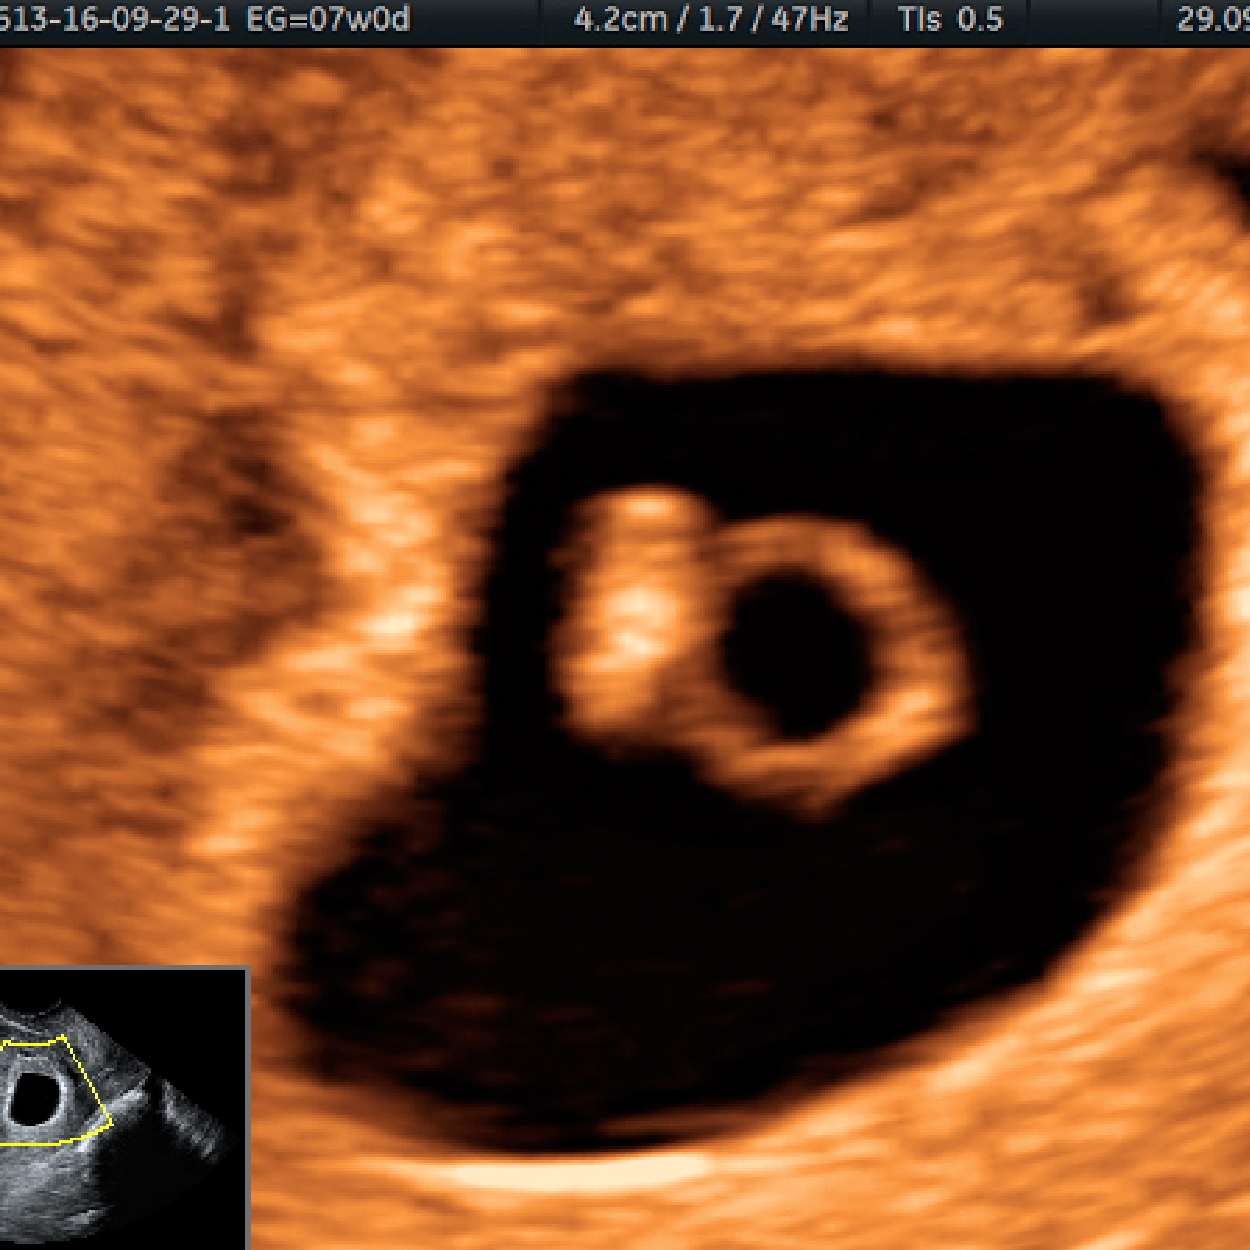

3. Confirmación de la vitalidad (latido cardíaco en el embrión/feto).

4. La detección de signos que nos indiquen que estamos ante la presencia de un embarazo fallido.

7. Evaluación del saco gestacional y del embrión antes de las 10 semanas.